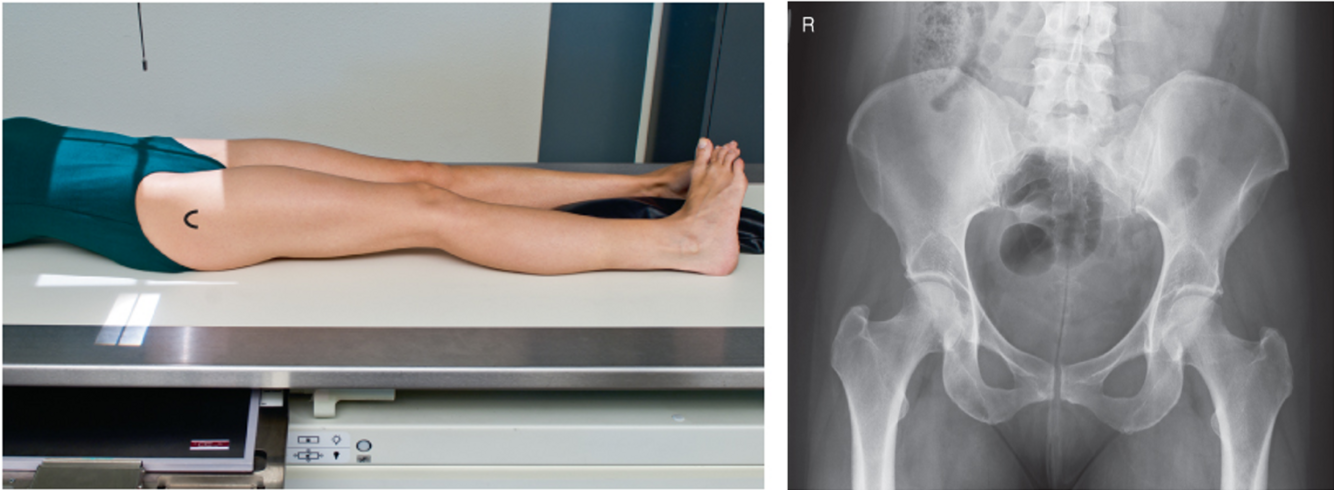

AP Pelvis

A

• IR 14x17 landscape. Minimum 40 SID (can use more distance for a larger pelvis to project divergent rays & decrease magnification)

• Pt supine, arms by side or on chest, can be done upright to evaluate joint spaces. Align MSP of pt to center of bucky/IR. Ensure pelvis is not rotated (ASIS equal). Separate legs and feet, internally rotate WHOLE LOWER EXTREMITY 15-20º. Use support devise if patient can’t hold position (tape/sandbags). Suspend respiration

• CR perpendicular to IR directed midway between between the level of ASIS & pubic symphysis (2” below ASIS). Ensure top of crest is in light field. Collimate to 4 sides of anatomy